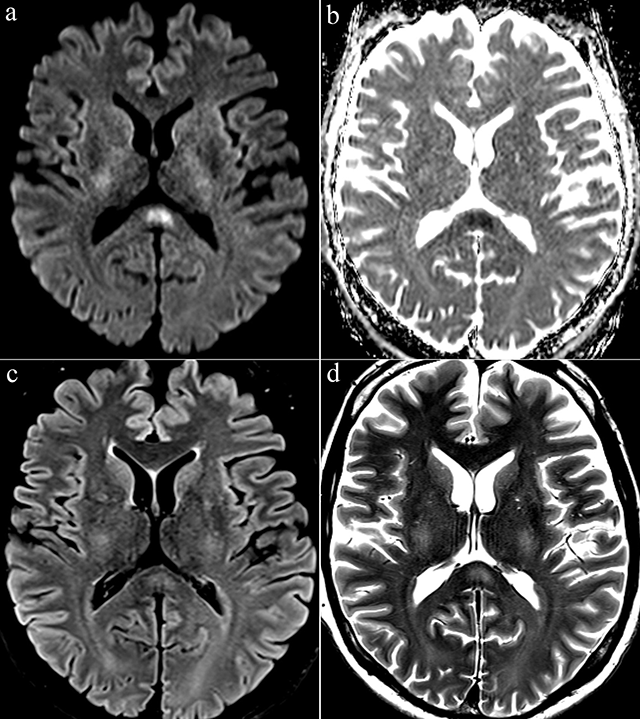

Figure 1

Axial diffusion-weighted image (b = 1000 s/mm2) (a) showed a high signal intensity in the splenium of corpus callosum. Apparent diffusion coefficent (ADC) map image (b) showed a low ADC. Axial FLAIR (c) and T2-weighted images (d) showed a slight hyperintense signal at the same location.